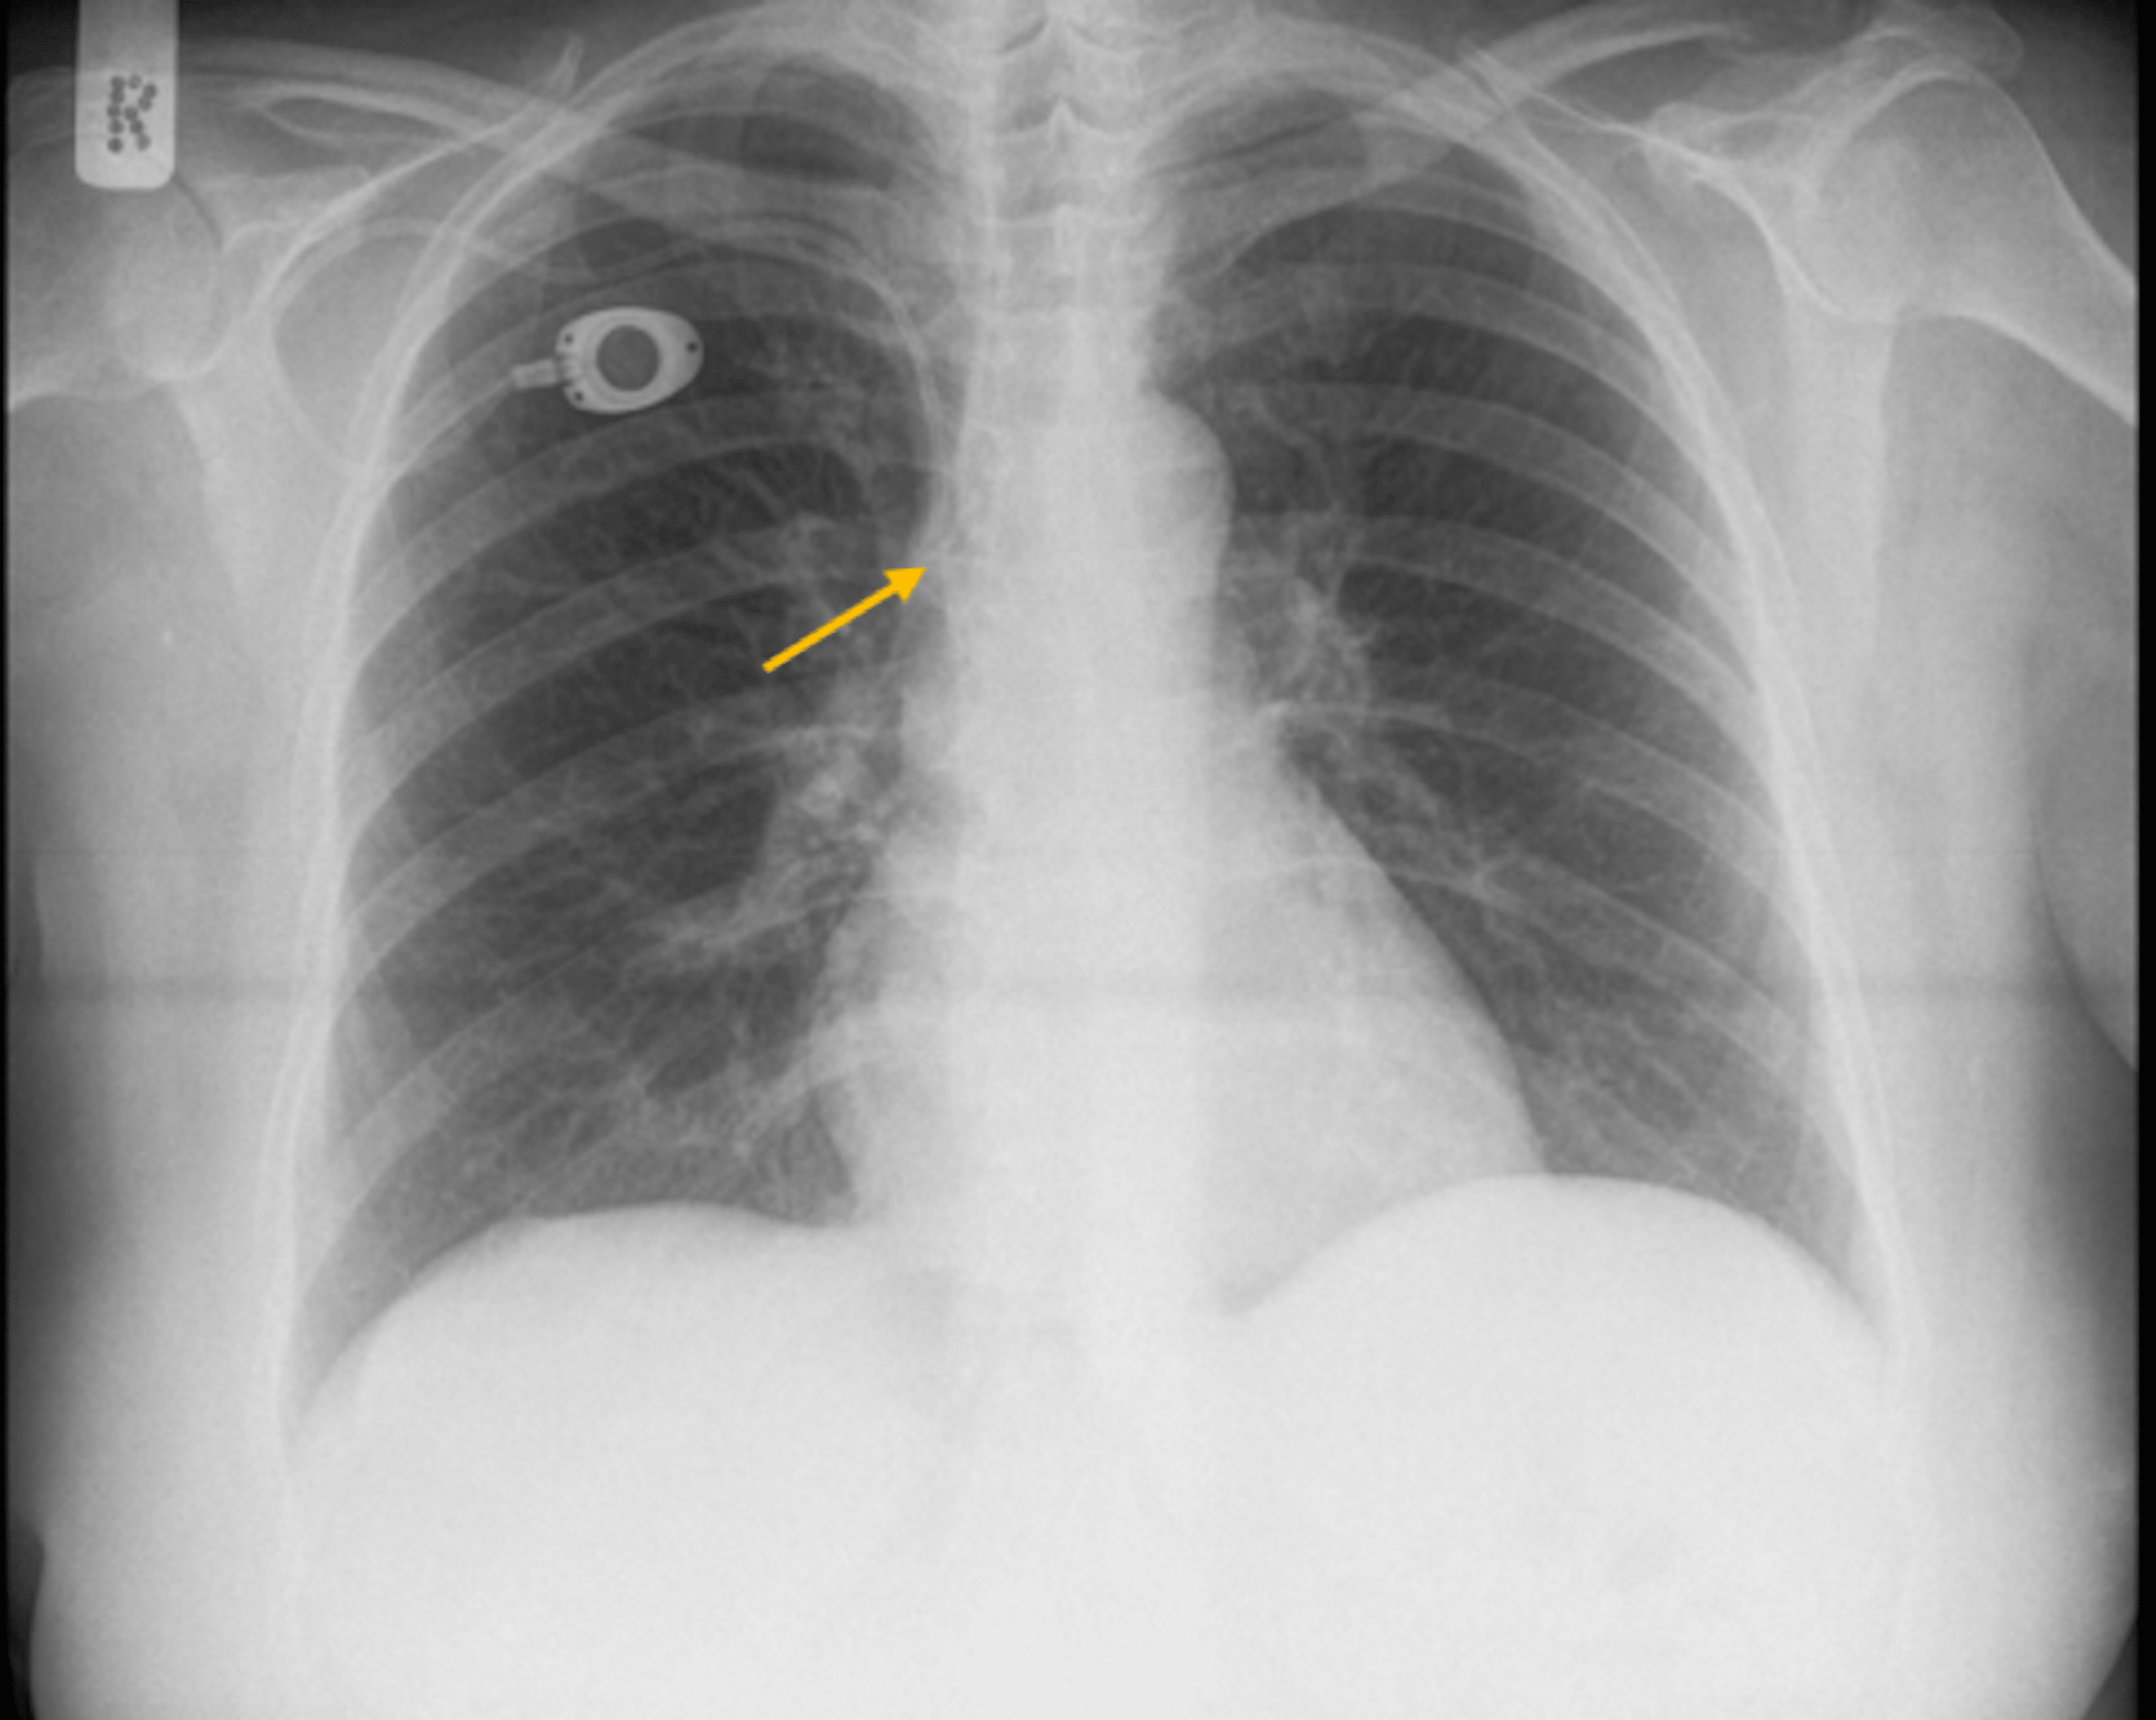

Cureus Asymptomatic Spontaneous Migration of the Tip of PortACath Internal Jugular Vein Catheter Complications ultrasonographic guidance for placement of internal jugular lines increases the likelihood of successful cannulation and reduces the. for adults and children, ultrasound guidance should be used to reduce mechanical complications in case of internal jugular access. subclavian, jugular, and femoral central venous catheterization are associated with infectious, thrombotic,. arterial puncture, hematoma, and pneumothorax are the most. Internal Jugular Vein Catheter Complications.